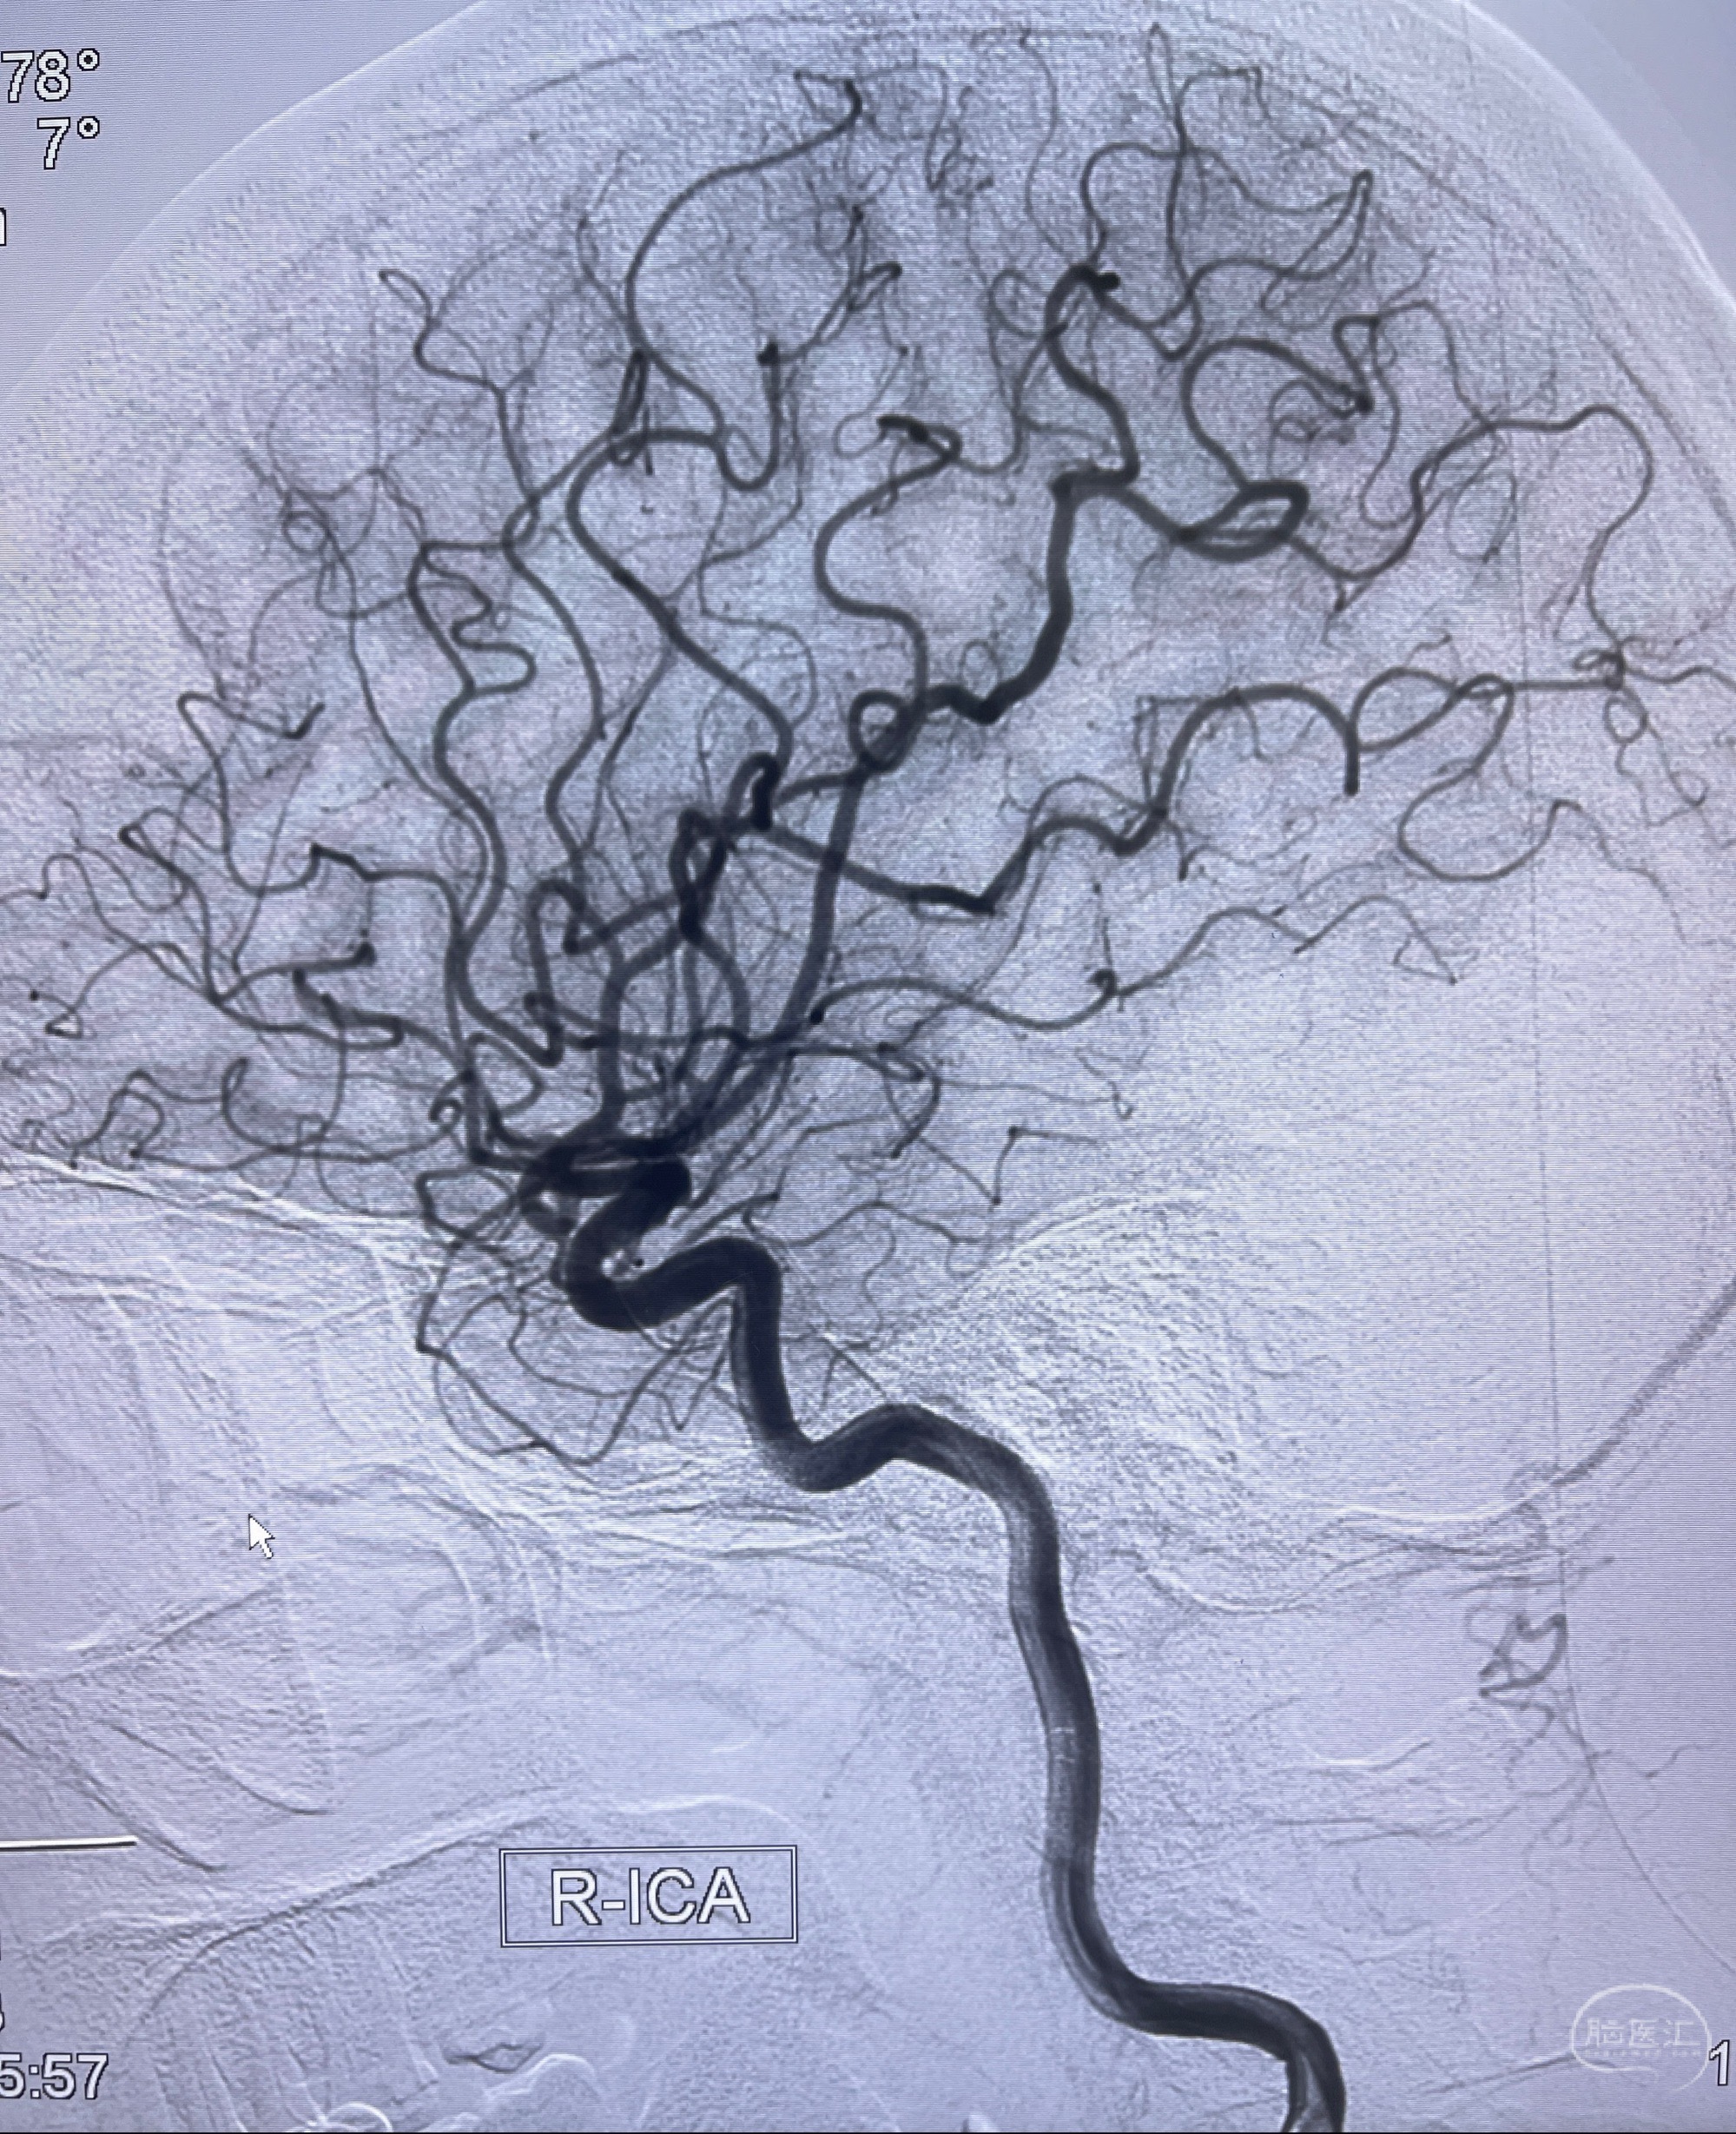

1.左侧大脑前动脉远侧段(A2-A5)动脉瘤

2023-08-23DSA:左侧前交通动脉瘤,左侧A3/4交界处多发动脉瘤